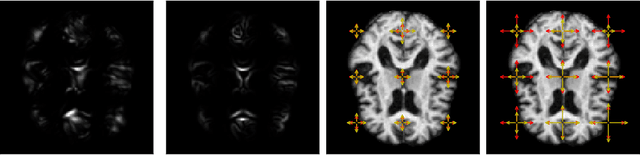

Abstract:Modelling deformation of anatomical objects observed in medical images can help describe disease progression patterns and variations in anatomy across populations. We apply a stochastic generalisation of the Large Deformation Diffeomorphic Metric Mapping (LDDMM) framework to model differences in the evolution of anatomical objects detected in populations of image data. The computational challenges that are prevalent even in the deterministic LDDMM setting are handled by extending the FLASH LDDMM representation to the stochastic setting keeping a finite discretisation of the infinite dimensional space of image deformations. In this computationally efficient setting, we perform estimation to infer parameters for noise correlations and local variability in datasets of images. Fundamental for the optimisation procedure is using the finite dimensional Fourier representation to derive approximations of the evolution of moments for the stochastic warps. Particularly, the first moment allows us to infer deformation mean trajectories. The second moment encodes variation around the mean, and thus provides information on the noise correlation. We show on simulated datasets of 2D MR brain images that the estimation algorithm can successfully recover parameters of the stochastic model.